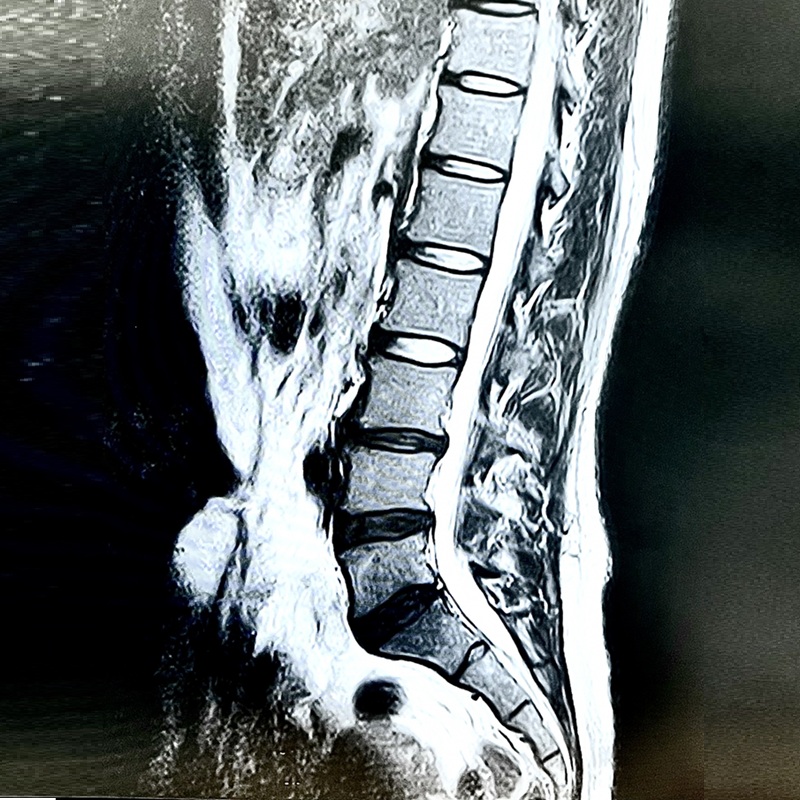

・椎間板ヘルニア

・脊柱管狭窄症

坐骨神経が圧迫されるメカニズム

1. 椎間板の変性や突出による圧迫